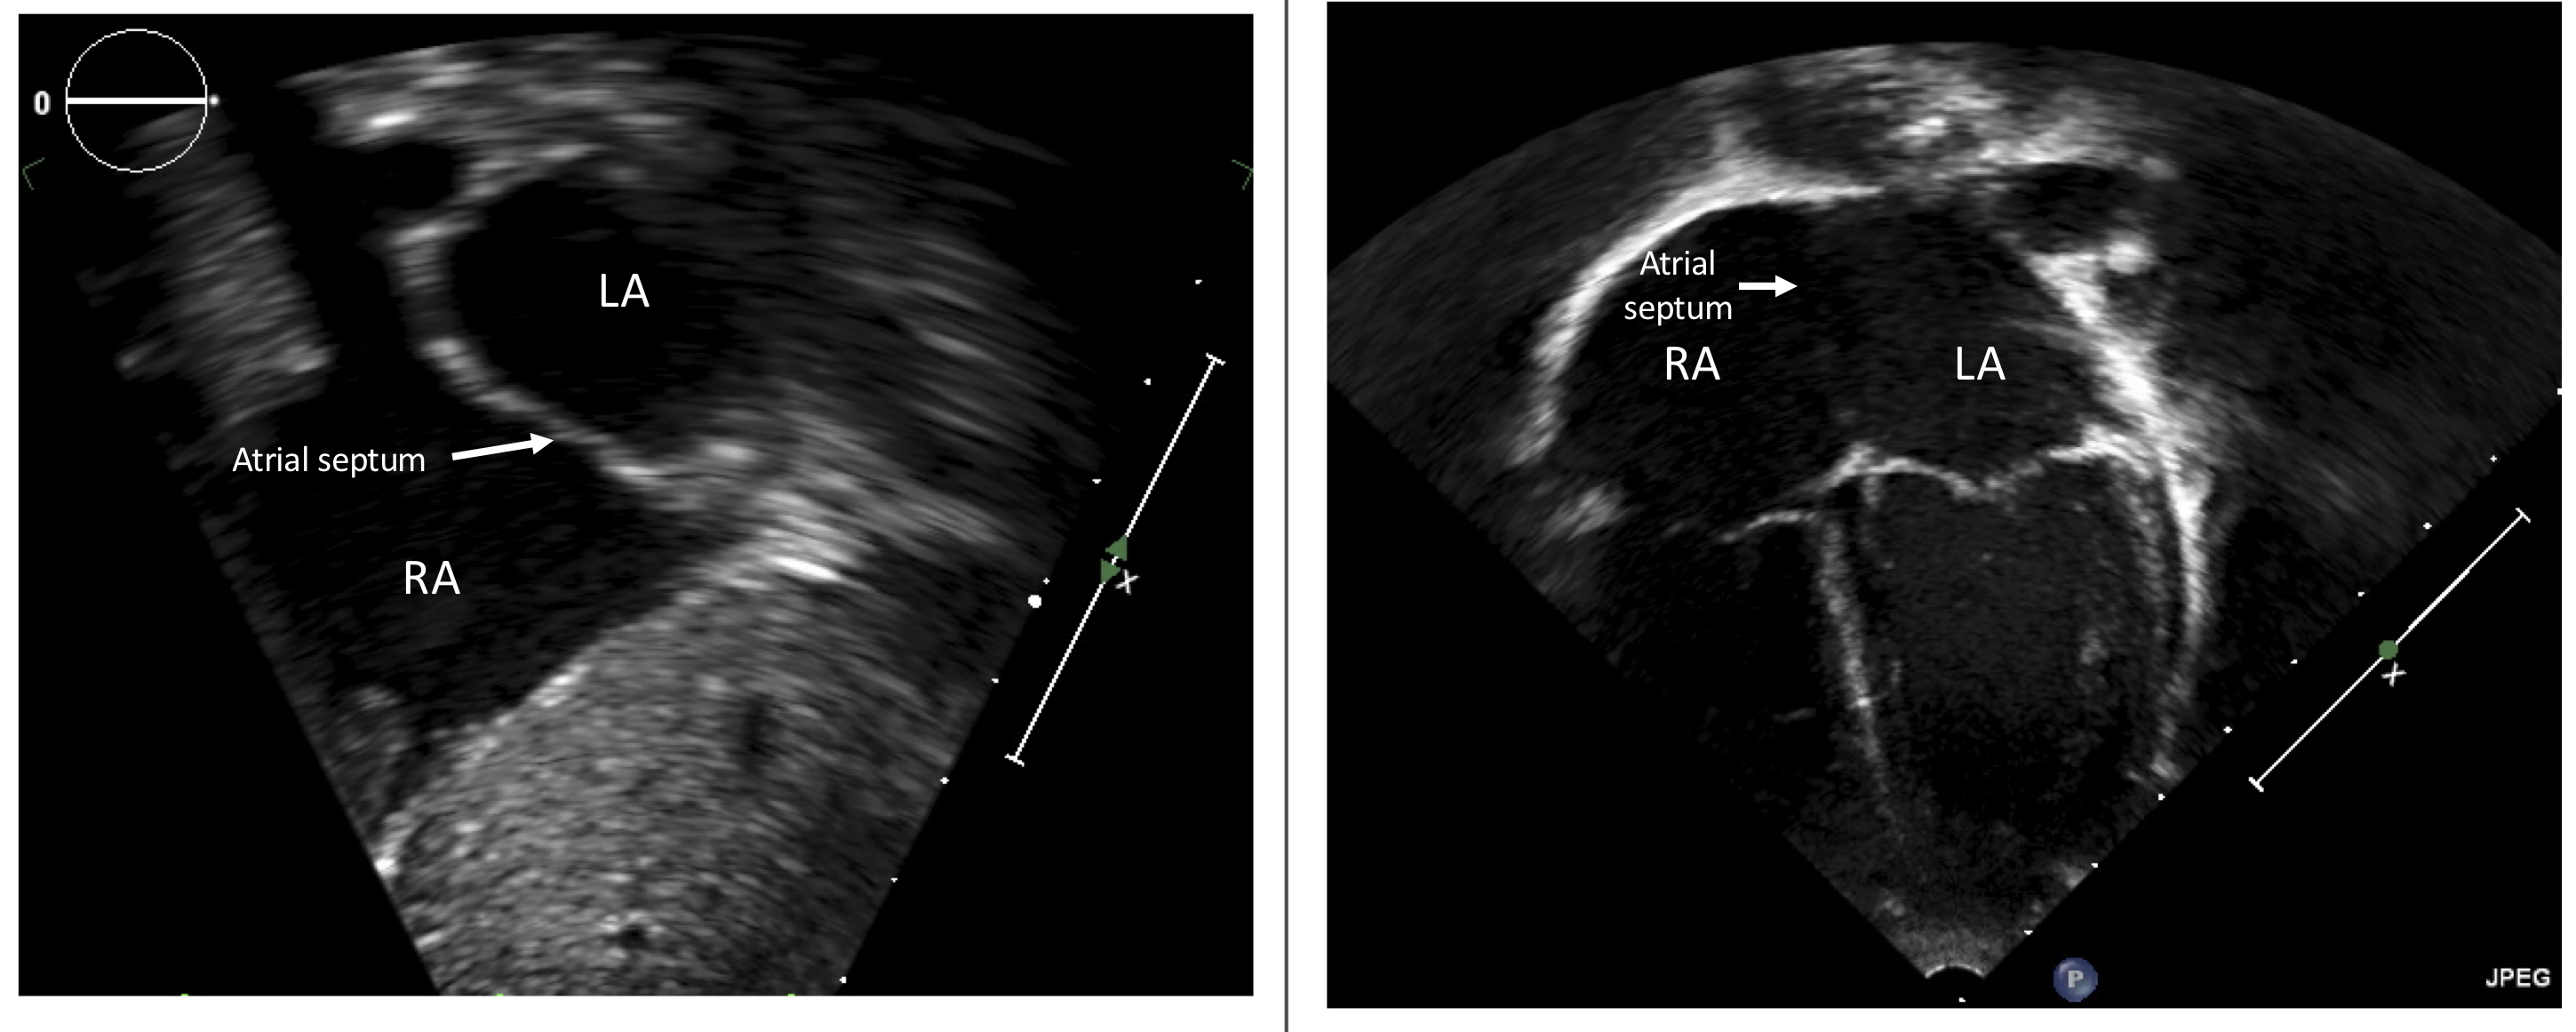

- Figure 4 shows two different images of a patient’s heart from two different windows and thus two different angles of insonation. From the subcostal sagittal window (left panel), the atrial septum is readily seen with no defect. From the apical 4 chamber view (right panel), the atrial septum is poorly seen and may appear to be deficient. Why? (Answer)

Images for Review Question 3. RA = right atrium; LA = left atrium.